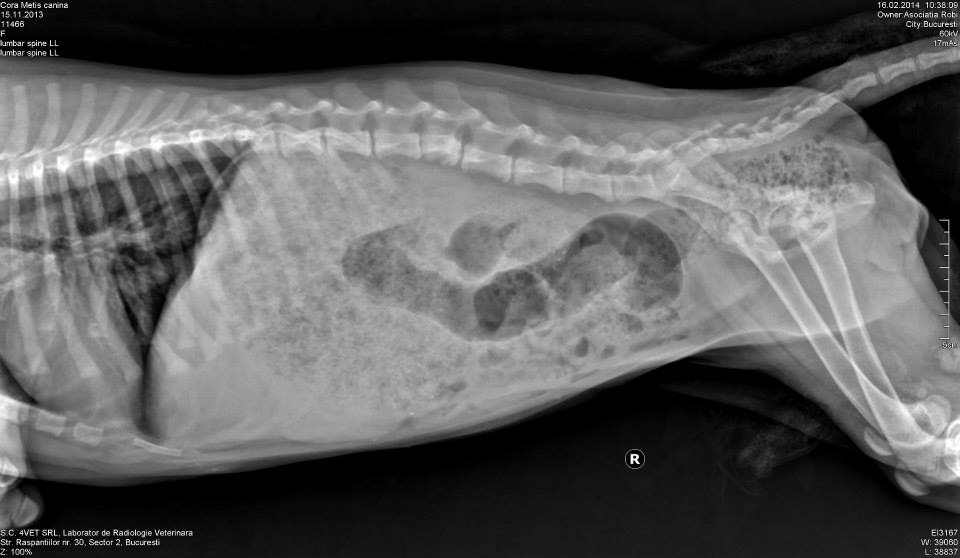

cora 2E posibil ca micuta Cora sa aibe noroc. Radiografiile facute au aratat ca are :

„fractura corp vertebral L3 cu proces secundar de stabilizare prin depunere de calus ceea ce denota un traumatism mai vechi. Nu are grad de lateralizare sau suprapunere”.

I-a fost recomandat examen RM regiunea L3 pentru aprecierea maduvei spinarii si modificarilor secundare.